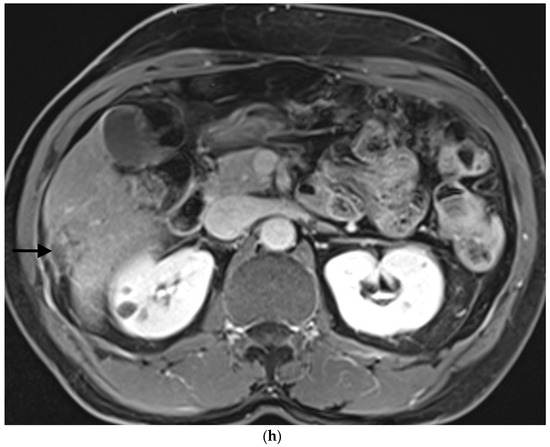

- Sandomenico, F.; Arpaia, V.; De Rosa, F.; Catalano, O.; Buonaiuto, R.A.; Notarangelo, M.; Iovino, M.; Giovine, S.; Brunetti, A.; Scaglione, M. Spontaneously ruptured hepatocellular carcinoma: Computed tomography-based assessment. Diagnostics 2023, 13, 1021. [Google Scholar] [CrossRef]

- Kim, H.C.; Yang, D.M.; Jin, W.; Park, S.J. The various manifestations of ruptured hepatocellular carcinoma: CT imaging findings. Abdom. Imaging 2008, 33, 633–642. [Google Scholar] [CrossRef] [PubMed]